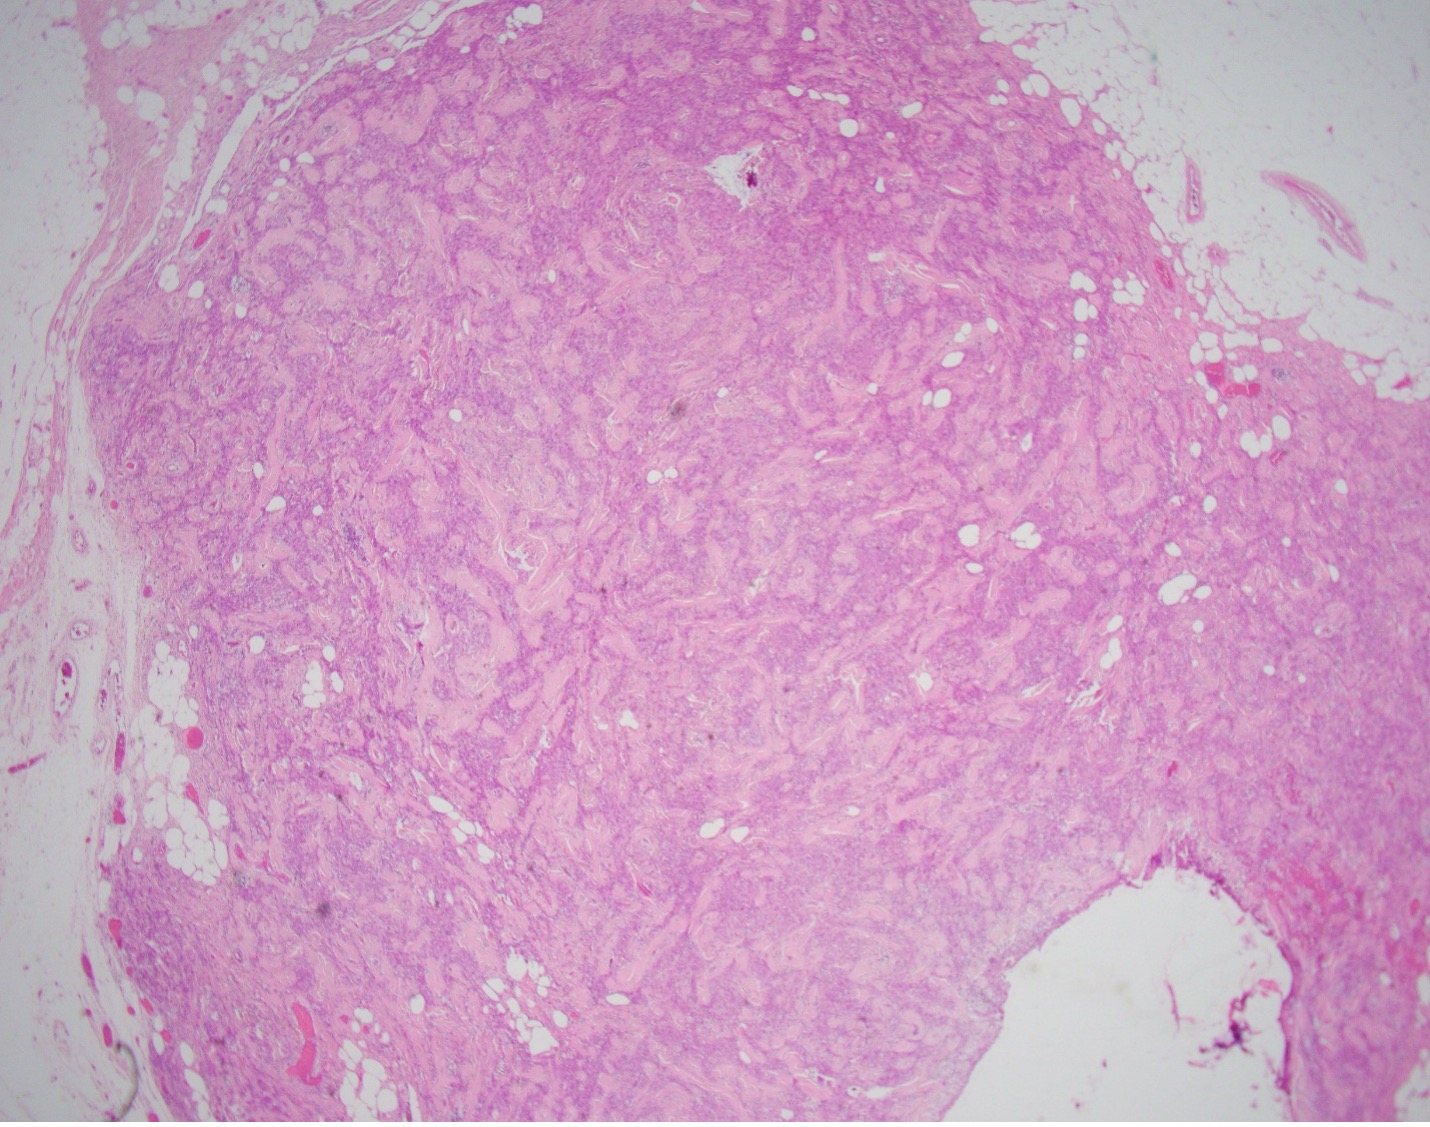

The patient is a 81-year-old male with a palpable breast mass. Imaging demonstrated an oval parallel mass with indistinct margins measuring 14 x 10 x 13 mm in the right breast at 1 o'clock located 1 cm from the nipple. A lumpectomy was performed and representative sections are shown.

Myofibroblastoma (MFB) is an uncommon myofibroblastic lesion, typically seen in older patients. It occurs in both males and females and usually presents as a slow growing, palpable, painless breast mass. Most lesions are small, 1-4 cm; however, cases of giant myofibroblastomas have been reported. Histologically, the lesion is characterized by a well-circumscribed mass composed of spindle cells intermixed between bundles of hyalanized collagen. Because the neoplasm is myofibroblastic in origin, immunohistochemical markers such as Smooth Muscle Actin (SMA), Muscle Specific Actin (MSA), and Desmin are characteristically positive. Myofibroblastomas are also typically positive for CD34, estrogen receptor (ER), progesterone receptor (PR), and androgen receptor (AR). The cells of interest are negative for cytokeratins. Genetically, the entity is characterized by loss of 13q14 and 16q. As a result, there is inactivation of genes RB1 and FOXO1, and as such, loss of Rb expression via immunohistochemistry. Treatment typically consists of surgical excision with no additional therapy required.

All of the other answer choices may be considered in the differential diagnosis, especially on biopsy. Metaplastic carcinomas can be comprised of spindle cells with or without an epithelioid component. However, the stromal collagen is typically not present and the cytology is much more pleomorphic with frequent mitosis and an infiltrative growth pattern. Additionally, metaplastic carcinomas will be positive for cytokeratin immunohistochemistry and negative for hormone receptors ER/PR/AR, CD34, and desmin/myofibroblastic markers. Phyllodes tumors are also neoplasms of stromal differentiation. Phyllodes tumors, however, show both the presence of spindle cells and benign epithelium, typically creating a “leaf-like” architecture. IHC is positive for CD34 but Rb staining is retained. Pseudoangiomatous stromal hyperplasia (PASH) usually doesn’t form a mass; however, it is a myofibroblastic lesion with a similar staining pattern, SMA, desmin, ER, and PR positive. Histologically PASH has a dense collagenous stroma with prominent slit-like spaces. Additionally, the characteristic genetic alterations found in MFB are not present.